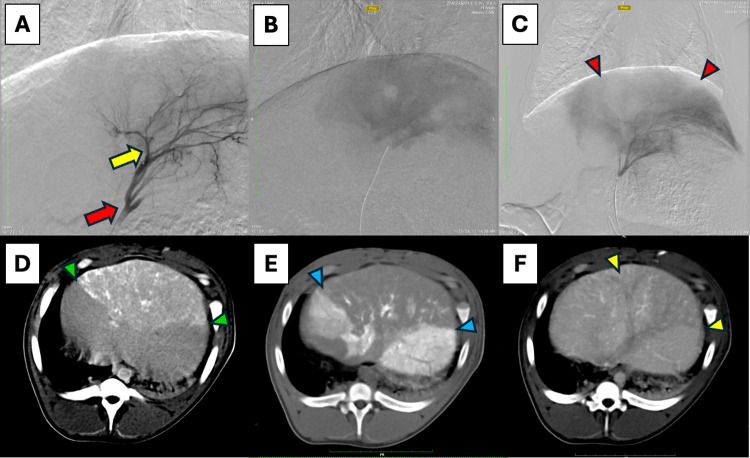

In vivo procedural imaging of thermoembolization using digital subtraction angiography (DSA) and computed tomography (CT): (A) DSA mapping of left hepatic artery, red arrow–tip of microcatheter, yellow arrow–tip of microcatheter in following magnified views. (B) DSA in late capillary phase showing blush of contrast in treated area (note: clear circular area is a draining hepatic vein en face devoid of contrast). (C) DSA in late capillary phase of same region post-treatment showing the nonperfused segment (absence of blush) denoted by red arrowheads surrounded by perfused tissue with contrast. (D) CT without contrast, immediately post procedure revealing the treated area with ethiodized oil/VPACl solution appearing as white and light gray areas (green arrowheads). (E) CT with contrast directly injected in the hepatic artery clearly shows enhancement in the surrounding perfused areas but not in the treated section (blue arrowheads). (F) CT with intravenous contrast in late portal venous phase showing differential portal perfusion in the treated area (yellow arrowheads) relative to surrounding liver.

An example case is shown in Figure with DSA done in 3 stages for the procedure. First we show the mapping of the target vascular bed in a lobe of the liver at an early time point, in which only the vessels are opacified by contrast. This is followed by an image taken several seconds later when the microcatheter has been navigated more distally into the lobar artery. The contrast has flowed from the vessels to the capillary level, and a diffuse blush in the tissue appears before washing away. The final DSA image was obtained after delivery of the thermoembolization solution, at the same catheter position and a corresponding time point to visualize the blush. A filling defect can be appreciated in the treated section and is manifest as an area that does not show the expected blush. The disruption of blood flow in the treated area caused by thermoembolization means that contrast is excluded from the area. Similarly, immediately after the procedure a CT scan was obtained, this time without contrast. Due to the radiopaque property of the ethiodized oil, the treated area is revealed as a wedge-shaped area in white and shades of light gray. A subsequent CT scan obtained shortly after contrast was injected through the microcatheter in the artery just upstream of the area reveals a large perfusion defect compared to the contrast flowing antegrade through the surrounding untreated tissues. Finally, a delayed portal venous phase image from a scan in which contrast was given intravenously reveals again the wedge-shaped defect. Importantly, this defect illustrates that the arterial delivery is also impeding portal venous flow in addition to the disruption on the arterial side. The dual blood supply of the liver has therefore been impacted significantly by the thermoembolization procedure.